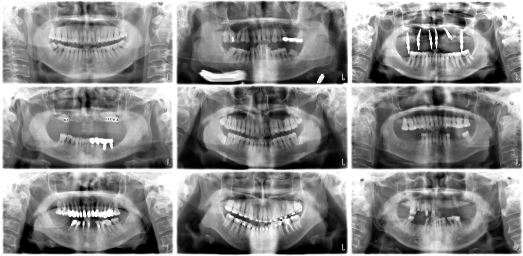

Refer to caption

Figure 1: Variation in dental panoramic X-ray structures across the DC1000 dataset, showing patients with full dentition, missing teeth, and braces.

There are studies in the literature that have exhibited strong performance. But most of them only use CNNs and do not systematically compare with Transformers, and Mamba-based models. In this field, it remains unclear whether architectural complexity truly translates into better performance for dental applications. To study the research question, we perform a comprehensive benchmark on the DC1000 dataset to rigorously study different segmentation architectures under the same experimental settings. Figure 1 shows the structural variability across the dataset, showcasing cases with full dentition, missing teeth, and orthodontic appliances. These examples highlight the real-world challenges of panoramic radiographs, where anatomical variation, metallic artifacts, and inconsistent contrast complicate automatic caries detection. The main contributions of this work are as follows: